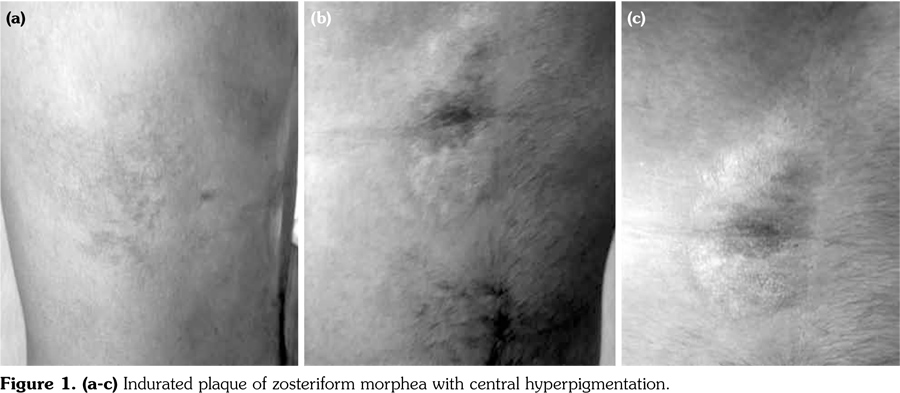

virus tested negative for immunoglobulin M, but positive for immunoglobulin G. Anti-nuclear antibody, anti-human immunodeficiency virus, first-tier immunoglobulin M and immunoglobulin G enzyme immunoassays for Borrelia were negative. A skin biopsy revealed an interstitial lymphoplasmacytic infiltrate which surrounded eccrine coils and distributed among separated deep dermal thickened, hypocellular and swollen collagen bundles, and papillary dermal collagen elastic fibers (Figure 2). Laboratory studies including blood cell count, serum chemistry, and autoantibodies (antinuclear antibodies and anti- Scl-70 also called anti-topoisomerase 1) were all normal or negative. Clinical and pathological features were consistent with the diagnosis of morphea. A written informed consent was obtained from the patient.